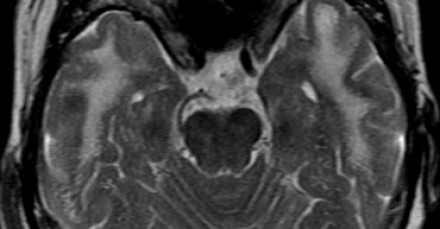

圖片十四:萊姆病患者中MS樣的病灶

MRI成像要點:2-3毫米大小病灶,與MS的病灶類似。患者有皮膚紅斑和流感樣疾病。其他特征包括:脊髓高信號,CN7(神經(jīng)根入腦干處)增強。